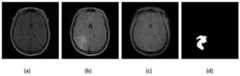

图5cGAN生成的人工低级胶质瘤图像:Figure 5 Artificial low-grade glioma image generated by cGAN:

(a)pre-contrast;(b)FLAIR;(c)post-contrast;(d)ground truth;(a) pre-contrast; (b) FLAIR; (c) post-contrast; (d) ground truth;

用低级胶质瘤训练集训练cGAN网络,利用训练好的网络生成人工胶质瘤图像,如图5所示。脑MR图像存在强度不均匀、不同序列强度范围不同和来自不同的采集协议等问题。结果表明,该生成器生成的图像在L1感觉上接近于真实图像。生成的胶质瘤图像与输入分割掩膜具有相似的形状特征,与真实的胶质瘤MR图像具有相似的纹理特征。输入手工分割掩膜与输出人工胶质瘤图像的虽然外观不同,但它们具有相同的底层结构和形状。生成结果验证了在图像到图像转换环境下cGAN生成各种胶质瘤图像的有效性。The low-grade glioma training set was used to train the cGAN network, and the trained network was used to generate artificial glioma images, as shown in Figure 5. Brain MR images have issues such as inhomogeneous intensity, different intensity ranges for different sequences, and different acquisition protocols. The results show that the images produced by this generator are close to real images in L1 sense. The generated glioma images have similar shape features to the input segmentation mask and similar texture features to real glioma MR images. Although the appearance of the input manual segmentation mask and the output artificial glioma image are different, they have the same underlying structure and shape. The generated results validate the effectiveness of cGAN in generating various glioma images in the context of image-to-image translation.